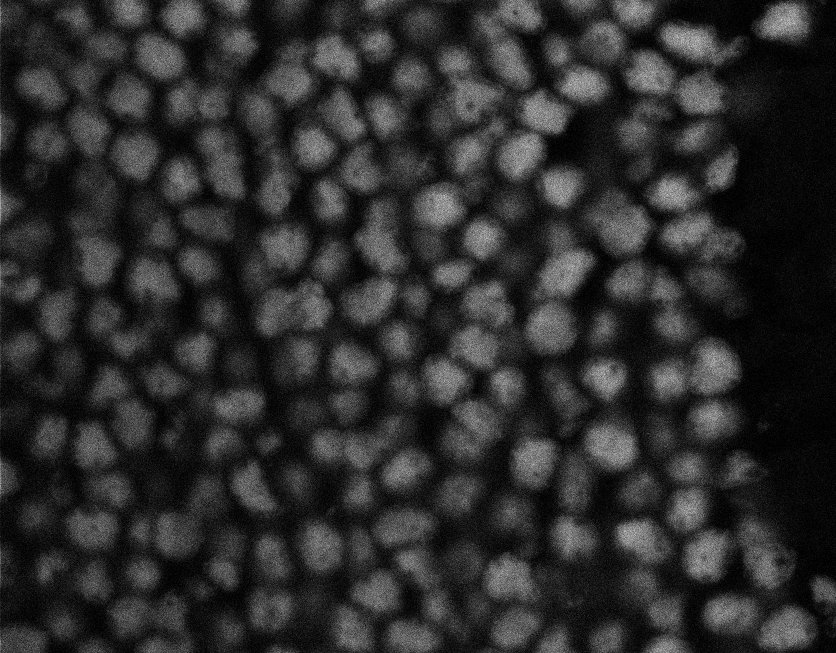

Healthy Choroid